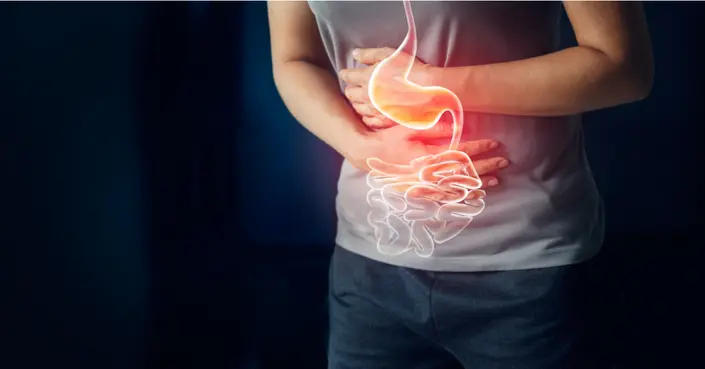

فهم القولون العصبي

القولون العصبي هو اضطراب مزمن يصيب الأمعاء الغليظة، ويُصنف على أنه متلازمة أكثر من كونه مرضًا واحدًا. يعاني المصابون به من مجموعة من الأعراض التي تختلف في شدتها وتكرارها من شخص لآخر. يتطلب التعايش مع القولون العصبي فهمًا عميقًا لكيفية تأثيره على كل من الجوانب الجسدية والنفسية للحياة اليومية.

الأعراض الجسدية للقولون العصبي

تتنوع الأعراض الجسدية للقولون العصبي بشكل كبير، وتختلف من شخص لآخر. يمكن أن تؤثر هذه الأعراض بشكل كبير على جودة الحياة اليومية.

آلام البطن والمغص

تُعد آلام البطن والمغص من أكثر أعراض القولون العصبي شيوعًا وإزعاجًا. غالبًا ما يشعر المصابون بهذه الآلام بعد تناول الطعام مباشرة، وقد تخف تدريجيًا بعد فترة. يتراوح الألم من خفيف إلى شديد، ويمكن أن يكون حادًا في بعض الأحيان.

الانتفاخ والغازات المزعجة

يُعد الانتفاخ في البطن والغازات الزائدة من الدلالات الواضحة للإصابة بالقولون العصبي. يمكن أن يكون الانتفاخ شديدًا لدرجة تجعل ارتداء الملابس المعتادة غير مريح. أما الغازات، فتُسبب إحراجًا وقلقًا اجتماعيًا كبيرًا، مما يدفع البعض إلى تجنب الأماكن العامة.